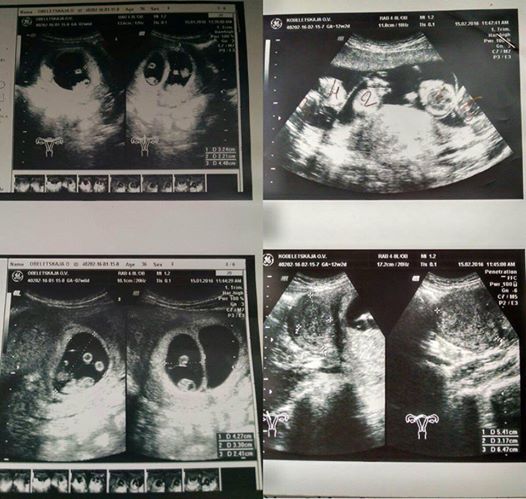

Amikor Oksana bement egy rutin ultrahang vizsgálatra, az orvos első hallásra hihetetlen hírekkel ajándékozta meg. “Amikor láttam a döbbenetet az orvos arcán, a szívem megállt egy pillanatra,” emlékeztetett vissza Oksana. “Aztán azt mondta az orra alatt: “Te biztosan díjat fogsz kapni ezért.” Úgy látszik, egymagam fogom növelni a nemzeti születési rátát…”

Az orvos megtette a bejelentést: “Látok öt magzatot. Talán hatot. Nehéz megmondani.”Rendkívül ritka, mondanom sem kell. Ötös ikrek csak egyszer fordulnak elő 55 millió terhességből! Miközben a várandós anya feldolgozta ezt a rendkívüli hírt, az emberek izgatottan mesélték el egymásnak a történetét az egész klinikán. Egy orvos sem volt ott, aki valaha látott volna ilyet.